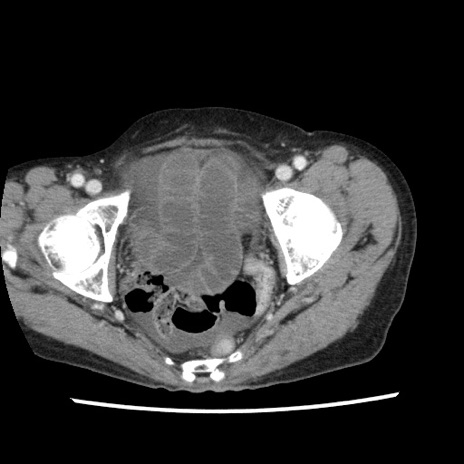

症例1(横断像)

【症例】80歳代女性

【主訴】腹痛

【現病歴】8時間前から腹痛あり来院。

【既往歴】糖尿病、脂質異常症、子宮体癌にて子宮全摘術

【身体所見】意識清明・会話良好だが腹痛で苦悶様、全腹部にわたって反跳痛と圧痛あり

【データ】WBC 13600、CRP 0.14、LDH 224、CK 90